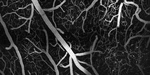

We design and build high-resolution microscopes to study the three-dimensional vascular and neuronal structures of the cortex at depths and resolutions pushing the limits of optical imaging.